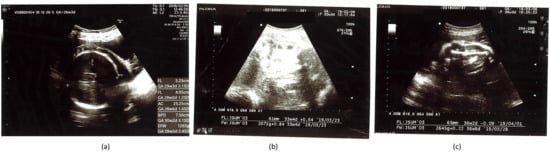

| Gestational Age | BPD (mm) | HC (mm) | AC (mm) | FL (mm) | EFBW (g) |

|---|---|---|---|---|---|

| 26w3d | 76 + 3.1 SD 97.5% | -- | 233 + 1.6 SD 95% | 52 + 2.1 SD 97% | 1265 + 2.4 SD 97% |

| 27w5d | 75 + 1.6 SD 90% | -- | 242 + 1.3 SD 90% | 56 + 2.3 SD 97% | 1421 + 2.0 SD 97% |

| 30w1d | 82 + 1.83 SD 90% | 301 ▲ 97% | 275 + 1.9 SD 95% | 60 + 1.9 SD 97% | 1947 + 2.4 SD 97% |

| 32w3d | 87 + 1.8 SD 90% | -- | 274 + 0.65 SD 50% | 61 + 0.64 SD 50% | 2071 + 0.84 SD 97% |

| 34w1d | 91▲ 50% | 339 ▲ 97% | 290 + 0.6 SD 10% | 67 + 1.5 SD 90% | 2480 + 1.2 SD 50% |

| 36w3d | 93 + 1.47 SD 50% | -- | 303 + 0.4 SD 10% | 65 − 0.09 SD 10% | 2645 + 0.22 SD 50% |

| 37w3d | 95 + 1.5 SD 50% | -- | 302 − 0.02 SD 10% | 73 + 1.75 SD 90% | 2886 + 0.44 SD 50% |